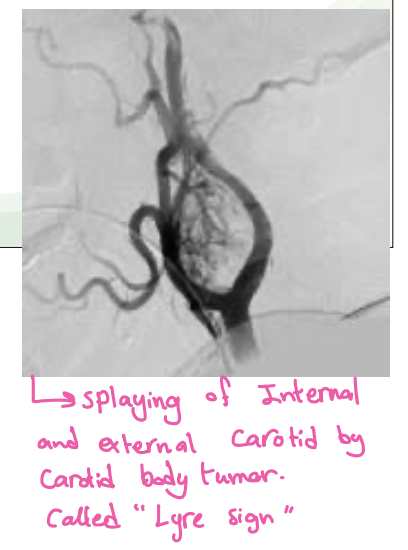

Arteriography-Shows the carotid bifurcation to be splayed open by the mass which is rich in vascularity

What is Lyre sign in CT scan?

angiogram - most likely carotid body tumour